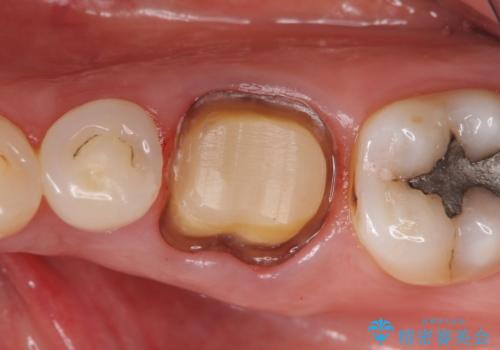

- 他院にて左下6の再根管治療を勧められ当院にいらっしゃった方の症例です。

再根管治療終了後、オールセラミッククラウンにて補綴を行いました。

- オールセラミッククラウン…¥100,000、仮歯…¥10,000、ファイバーコア…¥20,000費用は治療当時の料金となります